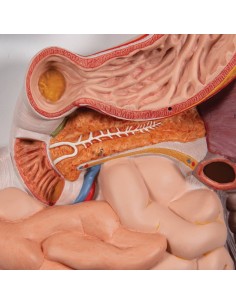

Dal cranio in 22 parti con incastri magnetici ai modelli di colonna vertebrale, da quelli di articolazioni a quelli di cuore, ogni pezzo della nostra collezione è progettato per un’immersione totale nello studio dell’anatomia umana. I nostri modelli, realizzati tramite scansioni di ossa vere, garantiscono un’esperienza tattile autentica e una fedeltà di peso quasi identica agli originali.

Essenziali per studenti e professionisti, i nostri modelli anatomici sono strumenti didattici che permettono di osservare le strutture anatomiche con precisione, eliminando la necessità di dissezioni o studi invasivi. Sono inoltre utili per spiegare ai pazienti le patologie, rendendo la comunicazione più efficace e risparmiando tempo prezioso.